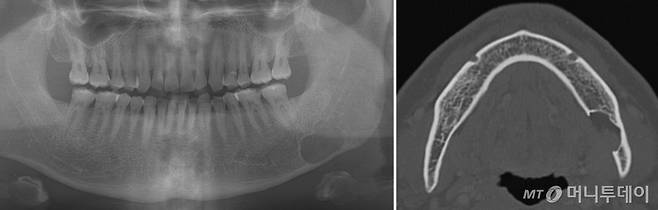

#한 치과에서 아래턱 왼쪽 어금니를 발치한 A씨(30대 후반)는 발치한 자리의 상처가 잘 낫지 않자 올해 3월 수지예치과로 옮겼다. 파노라마영상으로는 정확한 진단이 어렵다고 해서 CT(컴퓨터단층촬영)도 찍었다. 수지예치과는 영상치의학 전문의의 원격판독이 되는 곳이어서 다음날 진단결과를 받을 수 있었다. 판독결과는 골수염이었다. A씨는 바로 대형병원으로 옮겼다.

#비교적 치아관리를 잘해온 B씨(50)는 치주질환이 의심돼 지난해 11월 치과에 갔다가 찍힌 영상을 보고 깜짝 놀랐다. 왼쪽 아래턱에 누가 봐도 이상한 게 관찰돼서다. 치과 원장도 종양 같다며 서둘러 대학병원에 가볼 것을 권했다. 하지만 서울대치과병원의 영상판독 결과는 종양이 아니라 ‘하악골 설측 함요’였다. 단순히 뼈가 채워지지 않은 결손 부위였다.

치아가 상하거나 치주질환이 생기면 통상 치과에서 치료 전 파노라마영상을 찍는다. 이 영상에는 육안으로 보이지 않는 많은 정보가 담겨 있다. 아픈 증상이 없어 자각하지 못할 뿐 염증이 커지고 있거나 종양이 자라고 있기도 하다. 문제는 일반인은 물론 치과의사들도 이를 제대로 보지 못한다는 것이다. 치주질환처럼 흔한 증상은 아닌 데다 영상판독은 또 다른 전문분야이기 때문이다. 심각한 수술들을 매일 접하는 대학치과병원에서도 영상판독은 전문의에게 맡긴다.

허경회 서울대치과병원 영상치의학과 교수는 “사진상 물혹이나 양성종양 등의 특징적인 소견이 보여 동네치과에서 리퍼(refer·협진의뢰)해 내원하는 환자들이 있다”며 “상악동이 크게 보이거나 선천적으로 뼈가 결손된 경우인데 영상치의학 전문가는 이런 경우 치아뿌리를 둘러싼 하얀 치조백선을 같이 보면서 진단한다”고 설명했다.

메디파트너치과 영상센터에 따르면 선천적인 뼈의 결손 부위가 물혹처럼 보이는 ‘스타프네’(Stafne’s cyst)는 0.05%(11건), 뼈의 석회화가 심해 나타나는 골경화증 또는 골형성이상이 0.61%(134건) 등이다. 정 센터장은 “이러한 이상 소견들은 상급병원에 갈 필요가 없다”며 “하지만 일반인이 보기에도 이상하다고 볼 수 있기 때문에 전문적인 영상판독이 중요하다”고 말했다.